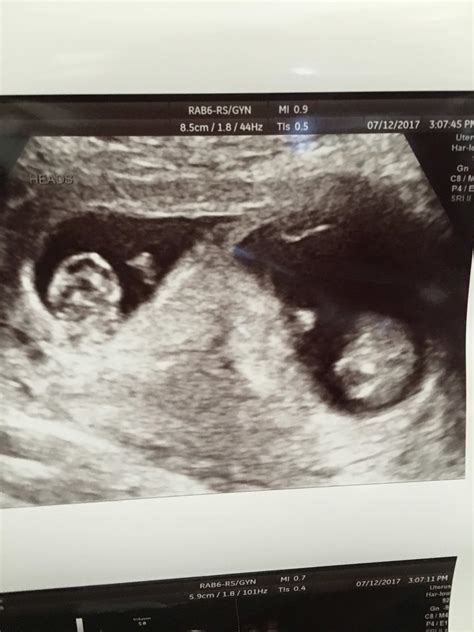

The Ultrasound 9 Weeks Twins scan is typically performed between 8 and 10 weeks of pregnancy. At this stage, the embryos are still very small, but significant developments are occurring. The primary goal of this ultrasound is to confirm the presence of two gestational sacs, each containing an embryo. This confirmation is crucial for determining the type of twin pregnancy—whether it is dizygotic (fraternal) or monozygotic (identical).

Two distinct gestational sacs Indicates dizygotic (fraternal) twins.

Single gestational sac with two yolk sacs Indicates monozygotic (identical) twins.

Detectable heartbeats Confirms the viability of the embryos.